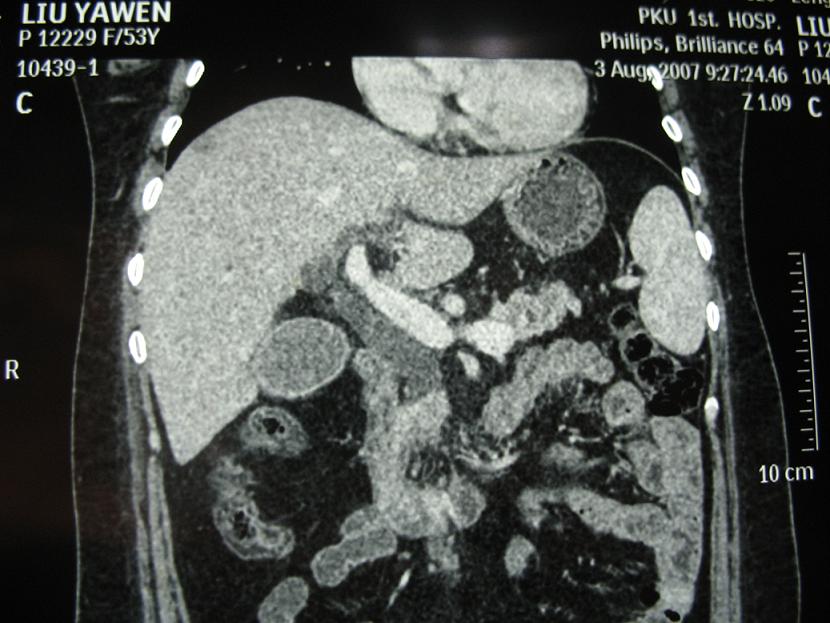

标题: CT17151:女 53岁 腹痛数月余 轻微黄疸 [打印本页]

女 53岁 腹痛数月余 轻微黄疸

1)考虑胰头癌。2)胆囊炎。

壶腹周围占位(钩突ca?)

胰腺钩突mt

考虑十二指肠乳突癌

支持胰腺钩突ca伴胆系梗阻,胆囊炎

考虑 胰头癌可能性大。

建议mrcp检查。